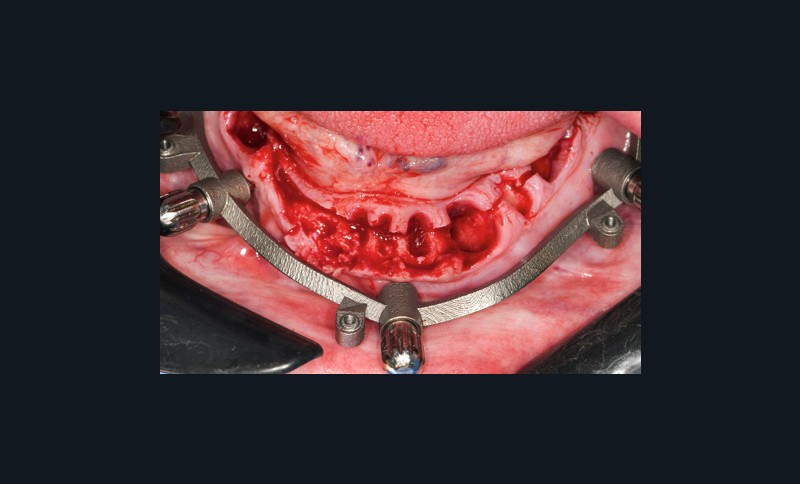

- appui muqueux : sa précision est inférieure. Réservé aux cas d’édentement total, il est conçu à partir d’un alignement avec une prothèse amovible complète comportant des marqueurs radio-opaques (fig. 5 à 8). Le risque d’imprécision est majoré par la dépressibilité de la muqueuse, la tuméfaction des tissus mous due à l’anesthésie, ou le positionnement initial en s’aidant de l’occlusion ;

- appui osseux : la mise en place nécessite un large lambeau et en fait…